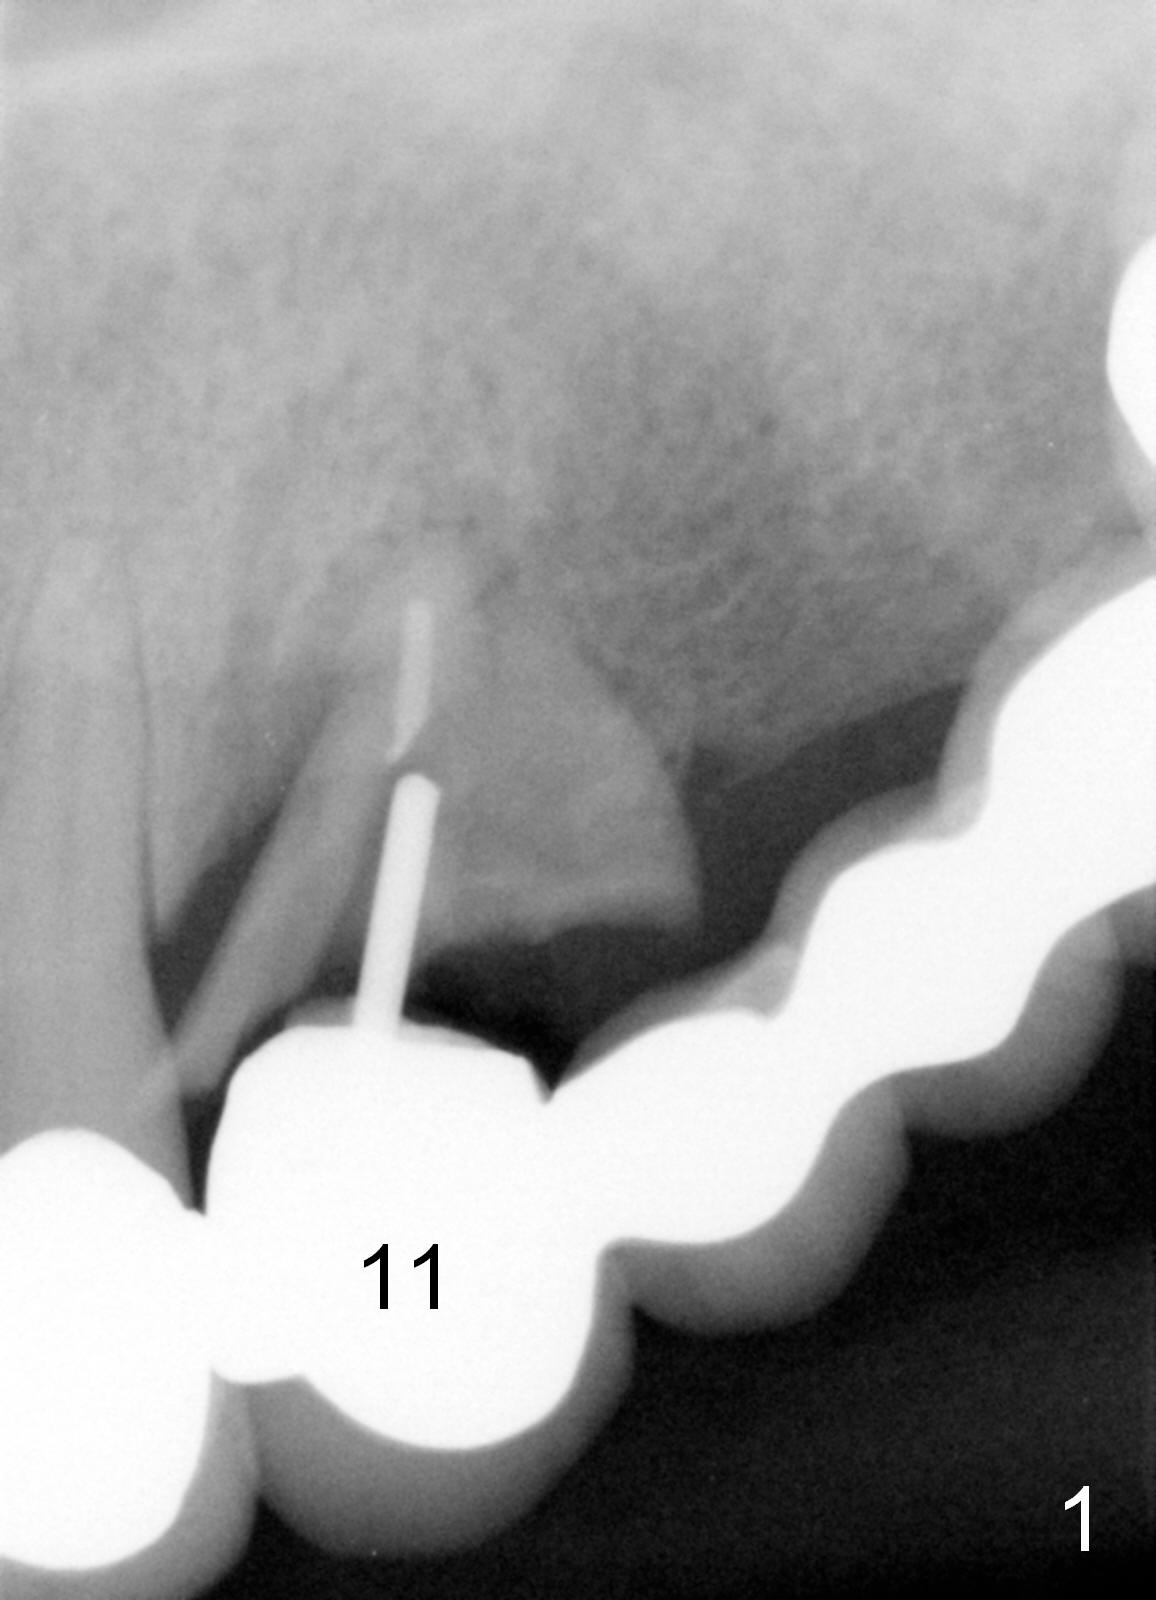

A 68-year-old female has had a long spanned FPD (fixed partial denture, bridge) for the last 2 years. It is loose (Fig.1,2). The patient is concerned about cosmetics, but has limited finance. The FPD dislodges when Alginate impression is being taken. The teeth #11 and 15 will be extracted and replaced immediately by implants (Fig.3,4). After placement of abutments, a 5-unit immediate provisional FPD will be fabricated if the implants achieve primary stability. Otherwise, an additional implant will be placed at the site of #13. There will be no occlusal contact.

The sockets will be treated with Metronidazole.